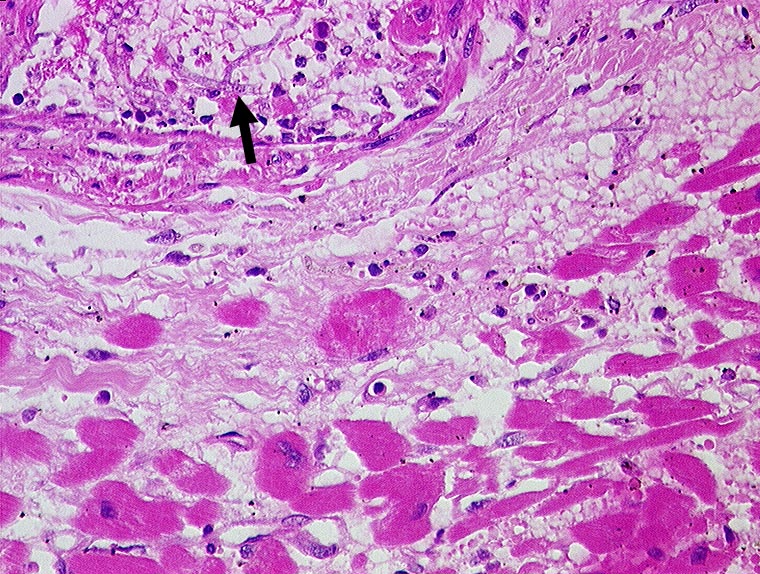

Aspergillussepsis mit Myokardbefall

Entzündung infektiös

Herz links

Kardiovaskuläres System

Aspergillushyphen in einem intramyokardialen Gefäss.

Aspergillussepsis. Chronische lymphatische Leukämie. Metastasierendes Spinaliom.